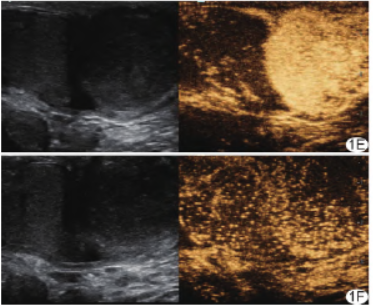

患者男,64岁,阴囊右侧坠胀不适3月余;既往无特殊病史。查体:阴囊右侧肿大,无触痛,表面皮肤无明显异常。超声:右侧睾丸中下极25mm×35mm实性低回声结节,内部回声不均,边界不清(图1A),CDFI于其周边及内部见点状血流信号,阻力指数(resistance index,RI)呈低阻型;超声造影呈“快进快退”等增强模式(图1B、1C);右侧睾丸向右移位约2cm,另于其左外侧见29mm×37mm实性较均匀低回声结节,边界清晰(图1D),CDFI于其周边及内部见点条状血流信号,RI呈低阻型;造影呈“快进慢退”高增强模式(图1E、1F);弹性成像示2个结节硬度均高于正常睾丸实质;提示阴囊内多发恶性结节(肉瘤?)。

图1 睾丸旁混合型脂肪肉瘤 A~C.右侧睾丸中下极肿物(A)于30s灌注达峰(B)、40s廓清(C);D~F.右侧睾丸左外侧肿物(D)于28s达峰(E)后缓慢消退(F) (RT:右侧睾丸;T:肿物)